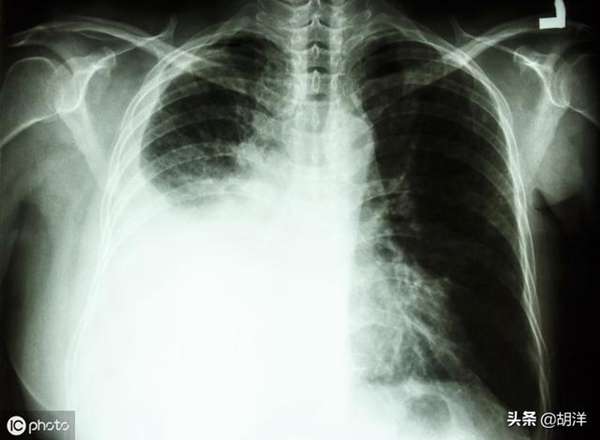

4.不明原因单侧胸腔积液 如果出现单侧胸腔积液,患者会表现为胸闷、气喘,这时候要考虑到肺癌可能,肺腺癌容易出现胸膜转移引起胸水的产生。结核性胸膜炎也会出现单侧胸腔积液,但一般年轻人多见。